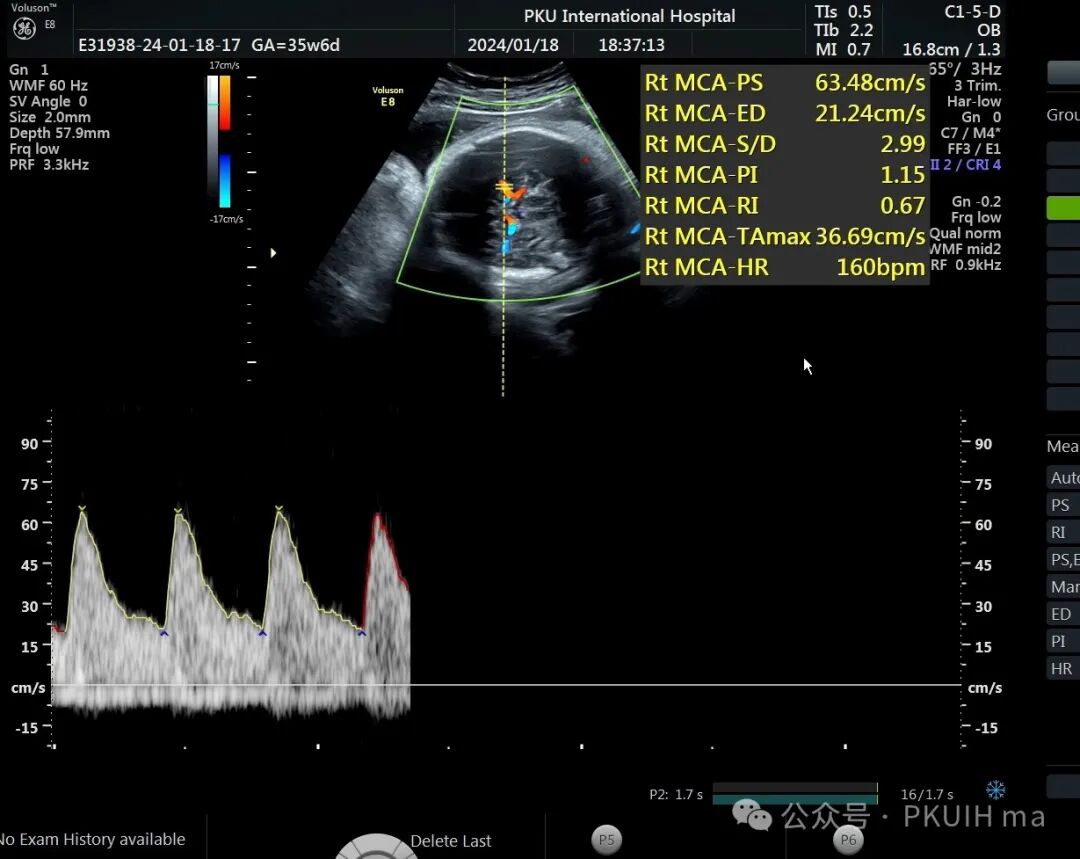

前两天碰到一孕妇胎动减少来诊,孕妇自述下午两点开始发现胎儿无明显胎动,吃了甜的食物和改变姿势还是不怎么动,随于下午六点左右来诊。超声发现胎儿绕颈两周以上且绕的较紧,检查中发现胎儿心率快,胎儿无明显胎动,绕颈处脐动脉血流加速时间延长,胎儿大脑中动脉阻力低,反复测量两侧大脑中动脉阻力均低。胎心监护也不好,随后产科采取紧急剖宫产。

反复测量左右两侧大脑中动脉阻力均低于第五百分位,考虑胎儿存在缺氧